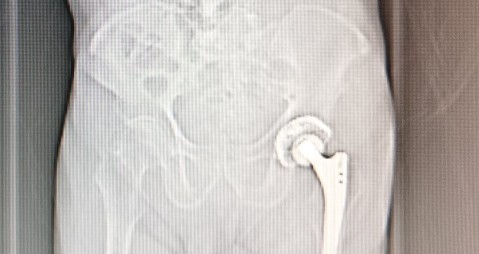

左侧股骨头置换